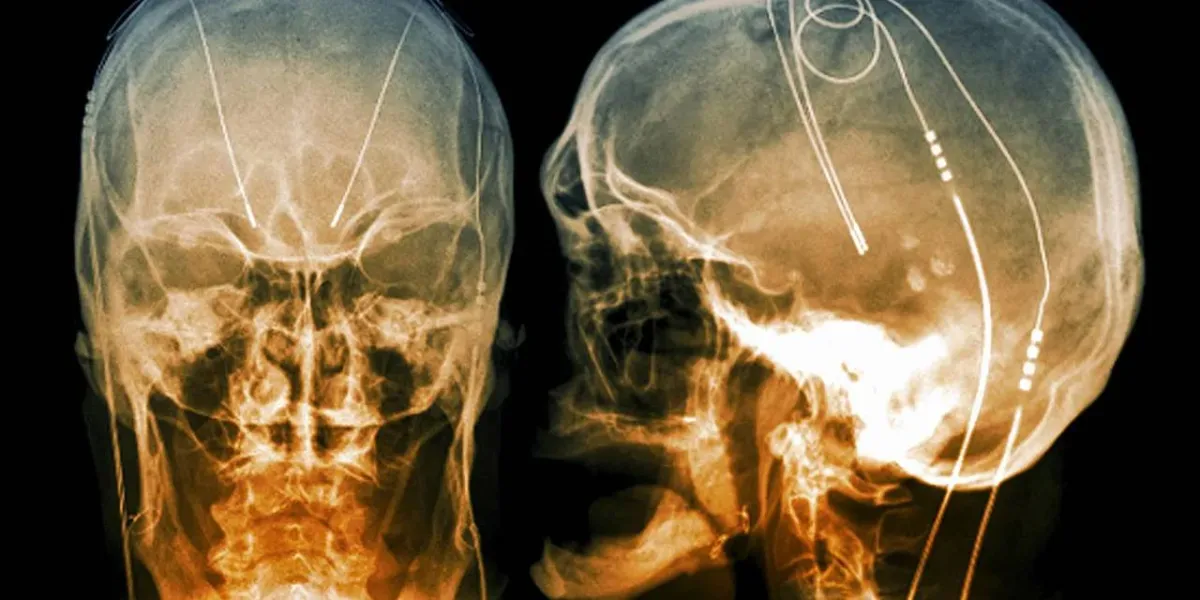

وبحسب التقرير يعتبر مستشفى ساوثميد الواقع في بريستول هو الأول في العالم الذي ينجح في زرع جهاز التحفيز العميق للدماغ (DBS)، حيث يعمل الجهاز عبر توصيل نبضات كهربائية مباشرة إلى المناطق المتضررة في الدماغ.

نظام العلاج الجديد يشتمل على نظام بطارية صغير للجهاز الذي يتم زرعه في الجمجمة، وبعدها يتم توصيل نبضات كهربائية للمناطق المستهدفة في الدماغ، في عملية لم تستغرق سوى 3 ساعات فقط.